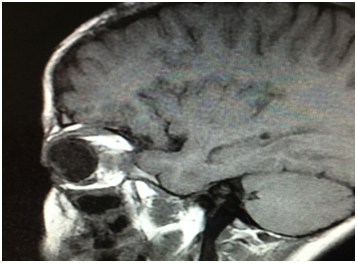

An orbital magnetic resonance imaging (MRI) revealed a well-defined cyst lesion sized 20×18×25 mm located in the intraconal space of the right orbit,hypointense on T1 weighted,hyper intense on T2 weighted, with marginal ring enhancement after an IV injection of gadolinium ethoxybenzyldiethylenetriaminepentaacetic(Figure 3).

The orbital MRI showsahypo intense cystic lesion on T1 weighted, hyper intense on T2 weighted, with marginal ring enhancement. The diagnosis of cyst capsule and intraconal lesions is facilitated with fat suppression.20